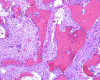

On immunohistochemistry, the epithelial islands are positive for cytokeratin AE1 and AE3 (Panel K and L). Both the spindle cell component and epithelial cells are positive for vimentin (Panel M).

Differentiated (osteofibrous dysplasia-like) adamantinomas are exclusively intracortical. The microscopic appearance of differentiated adamantinoma resembles osteofibrous dysplasia. Spindled cells with a storiform pattern mingle with fragments of bone. The bony fragments are typically rimmed by osteoblasts and exhibit gradual progression from woven to lamellar bone as one moves from the center to the periphery of the lesion. Epithelial islands can be seen interspersed focally within the aforementioned osteofibrous dysplasia-like stroma. The epithelial component is much less prominent than in the classic variety of adamantinoma. Immunohistochemistry for cytokeratin is a very useful adjunct to demonstrate these scattered epithelial elements and they can be very small and subtle as demonstrated in this case.